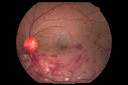

Retinal Artery Occlusion1084 viewsPatient comes in for eval on artery occlusions in both eyes. VA is 20/400, right eye and NLP, left eye. Fundus photos show paniretinal scars in the right eye with arterial narrowing and the left eye has arterial narrowing as well.